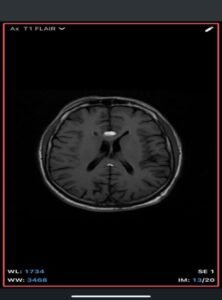

Intracranial dermoid cyst

A rare, congenital, benign lesion composed of mature adipose tissue located within the pericallosal cistern, closely related to the corpus callosum. It is a developmental anomaly rather than a true neoplasm.

Imaging Findings-

- MRI

- T1-weighted: Hyperintense (fat signal).

- T2-weighted: Variable, usually hyperintense; may show chemical shift artifacts.

- Fat-suppressed sequences: Complete signal suppression confirms fat composition.

- Post-contrast: No enhancement.